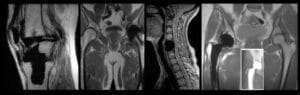

Magnetic Resonance Imaging (MRI) is a non-invasive medical imaging technique that uses a powerful magnetic field, radio waves, and computer processing to produce detailed images of the internal structures of the body. The core of an MRI machine is its magnet, which aligns the protons in the water molecules of the human body. When these protons return to their natural alignment after being perturbed by radio waves, they emit signals that are detected and transformed into images.

At the heart of every MRI system lies a strong magnet that creates a uniform and stable magnetic field. The process involves several steps:

- Alignment of Protons: In the presence of a strong magnetic field, hydrogen protons in the body align with the field.

- Radio Frequency Pulses: Radio waves are then used to disturb this alignment.

- Signal Detection: As the protons return to alignment, they emit radio signals that are detected by the MRI’s sensors.

- Image Reconstruction: A computer processes these signals and constructs detailed cross-sectional images of the body.